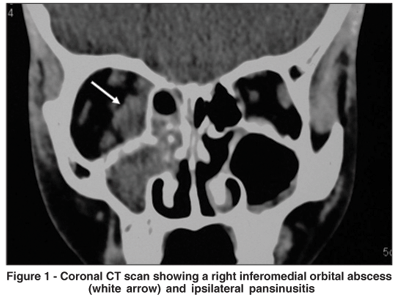

A previously healthy 11-year-old boy was evaluated for an acute inflammation in the right orbit. On examination, the right eye was proptotic (Hertel measurements were 22 and 12 mm) with swelling of the upper and lower eyelids. Ocular motility was limited in all gaze directions. Visual acuity was 20/40 of the right eye (OD) and 20/25 of the left (OS). Intraocular pressure was 40 mmHg in OD and 12 mmHg in OS. Orbital computed tomography (CT) disclosed a right inferomedial orbital abscess and ipsilateral pansinusitis (Figures 1 and 2). A cantholysis was performed on the OD during admission. The next day the boy underwent middle turbinate resection and ethmoidal and maxillary sinus drainage under general anesthesia. The orbit was approached by an inferior fornix transconjunctival incision. Abundant pus was aspirated from the orbit and sinuses. The culture grew positive for Group A b-hemolytic streptococci. The patient was treated with parenteral antibiotics (ceftriaxone and clindamycin) and five days after surgery he was discharged with full recovery of eye motility and complete resolution of proptosis. Four days after discharge the child presented with facial edema and signs of distress. A pediatric evaluation disclosed generalized edema and systemic hypertension (200 x 100 mmHg), with no other cardiac findings. Blood count, antinuclear antibody, rheumatoid factor, LE cells and serologic tests were within normal limits. Urinalysis showed hematuria and mild proteinuria. Seric complement component levels C3 and C4 were low. The patient was diagnosed as having acute poststreptococcal glomerulonephritis and was treated with furosemide, nifedipine and salt and fluid restriction. The outcome was favorable and after 12 days of hospitalization the boy was discharged without any signs of renal dysfunction, and with increase of complement levels afterwards.